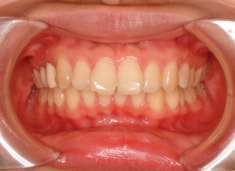

治療後(1年9ヶ月後)